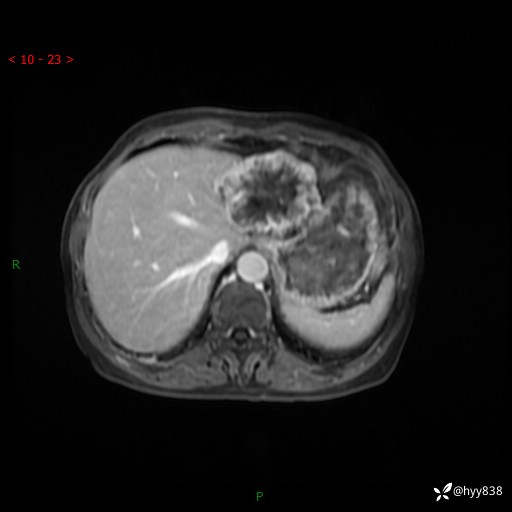

老年女性,偶然发现肝脏占位,综合各个序列,你考虑什么---结果公布

主诉:发现肝脏占位性病变2天

简要病史:患者2天前因“腰疼”至当地医院就诊时发现肝脏左叶占位性病变,无发热、畏寒,无皮肤黄染,无腹痛、腹泻,无恶心、呕吐、厌油等不适,今进一步诊治遂来我院就诊,门诊以“肝脏占位性病变性质待查”收入我科。 起病以来,患者精神、睡眠一般,饮食欠佳,二便正常,体力、体重无明显减轻,

辅助检查:MRI

临床诊断:肝占位

肝脏MRI平扫(同反相位)

T2WIfs+DWI

增强(动脉期+静脉期+延迟期)